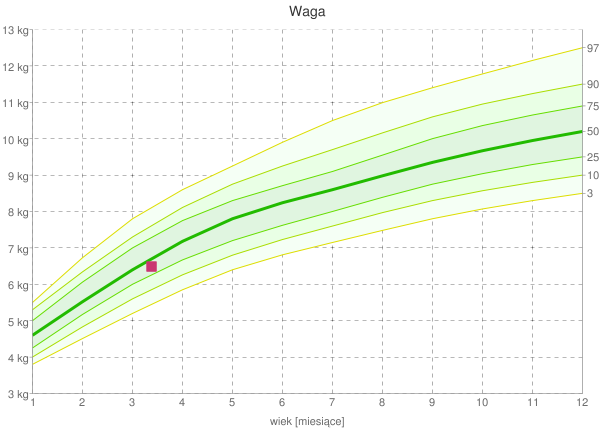

Moja waga na siatce centylowej.